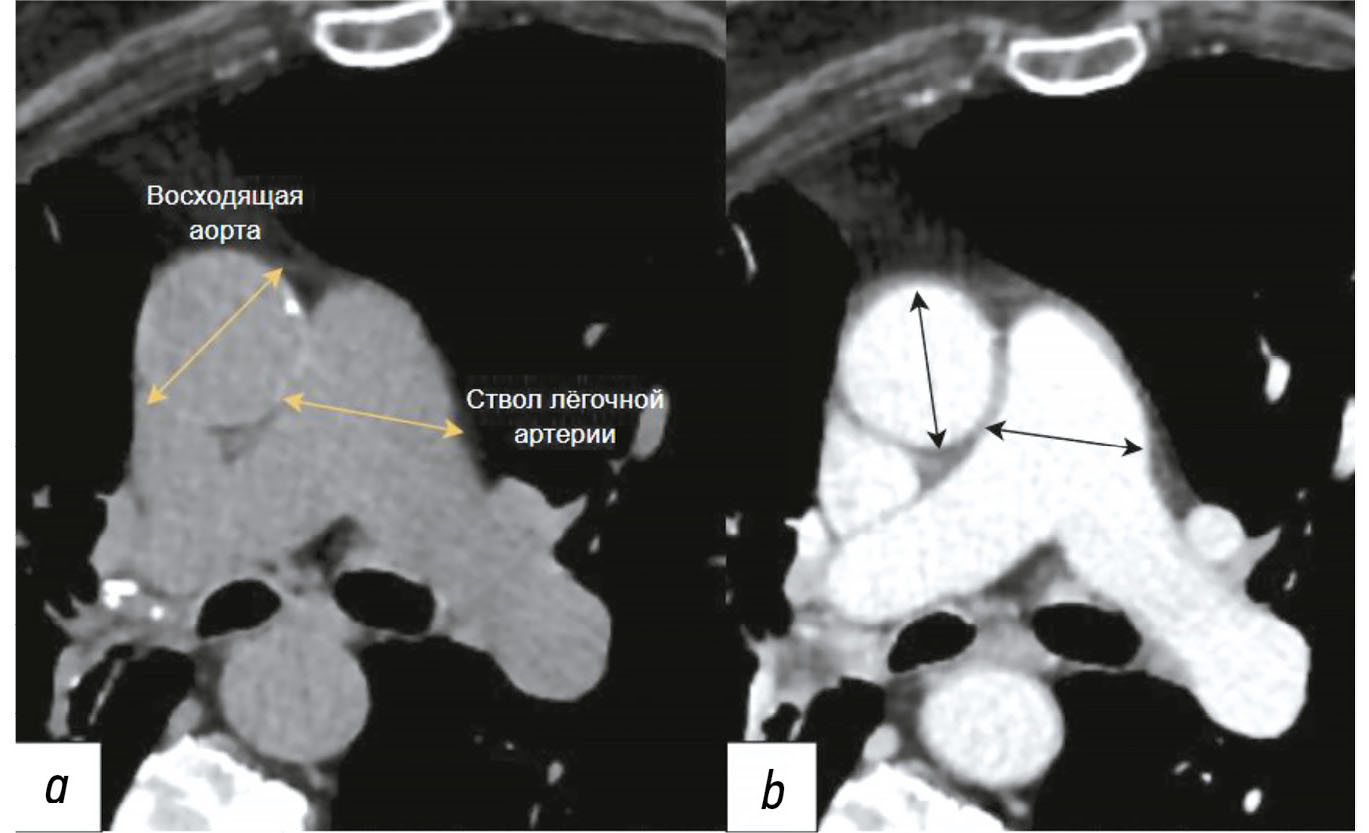

Диагностика аневризм грудного отдела аорты и патологического расширения лёгочного ствола с использованием компьютерной томографии органов грудной клетки и искусственного интеллекта: современные подходы и перспективы (научный обзор)

Аннотация

Ранняя диагностика аневризм грудного отдела аорты и патологического расширения лёгочного ствола имеет решающее значение для предотвращения серьёзных осложнений, включая разрыв сосудистой стенки и острую правожелудочковую недостаточность, а также для снижения смертности от сердечно-сосудистых заболеваний. В представленном обзоре рассматриваются современные подходы к визуализации этих патологий, с акцентом на использование компьютерной томографии в качестве «золотого стандарта». Отдельное внимание уделено внедрению технологий искусственного интеллекта, которые позволяют автоматически сегментировать сосудистые структуры, измерять их диаметр и проводить оппортунистический скрининг, выявляя скрытые патологии на ранних стадиях без необходимости проведения дополнительных исследований, что снижает нагрузку на врачей-рентгенологов и повышает качество медицинской помощи. Подробно анализируется опыт Московского эксперимента, в рамках которого использование технологий искусственного интеллекта в анализе медицинских изображений показало высокую чувствительность, воспроизводимость и сокращение времени описания. Несмотря на значительные преимущества, подчёркивается необходимость контроля результатов работы искусственного интеллекта специалистами для обеспечения точности и надёжности диагностики. Также отмечается актуальность адаптации алгоритмов к разным протоколам сканирования и популяционным особенностям. Кроме того, подчёркивается важность междисциплинарного взаимодействия кардиологов, рентгенологов, инженеров-данных и разработчиков программного обеспечения для для эффективного внедрения в рутинную клиническую деятельность. В заключение делается вывод о значительном потенциале технологий искусственного интеллекта для повышения качества диагностики и подчёркивается необходимость дальнейших клинических исследований и стандартизации методик для их успешной интеграции в повседневную практику.

286-301